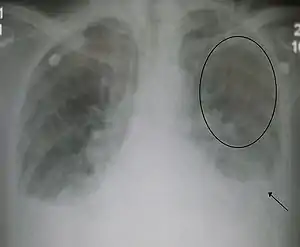

| Acute interstitial pulmonary edema. Note enlarged heart size, apical vascular redistribution ( circle ), and small bilateral pleural effusions ( arrow ). | |